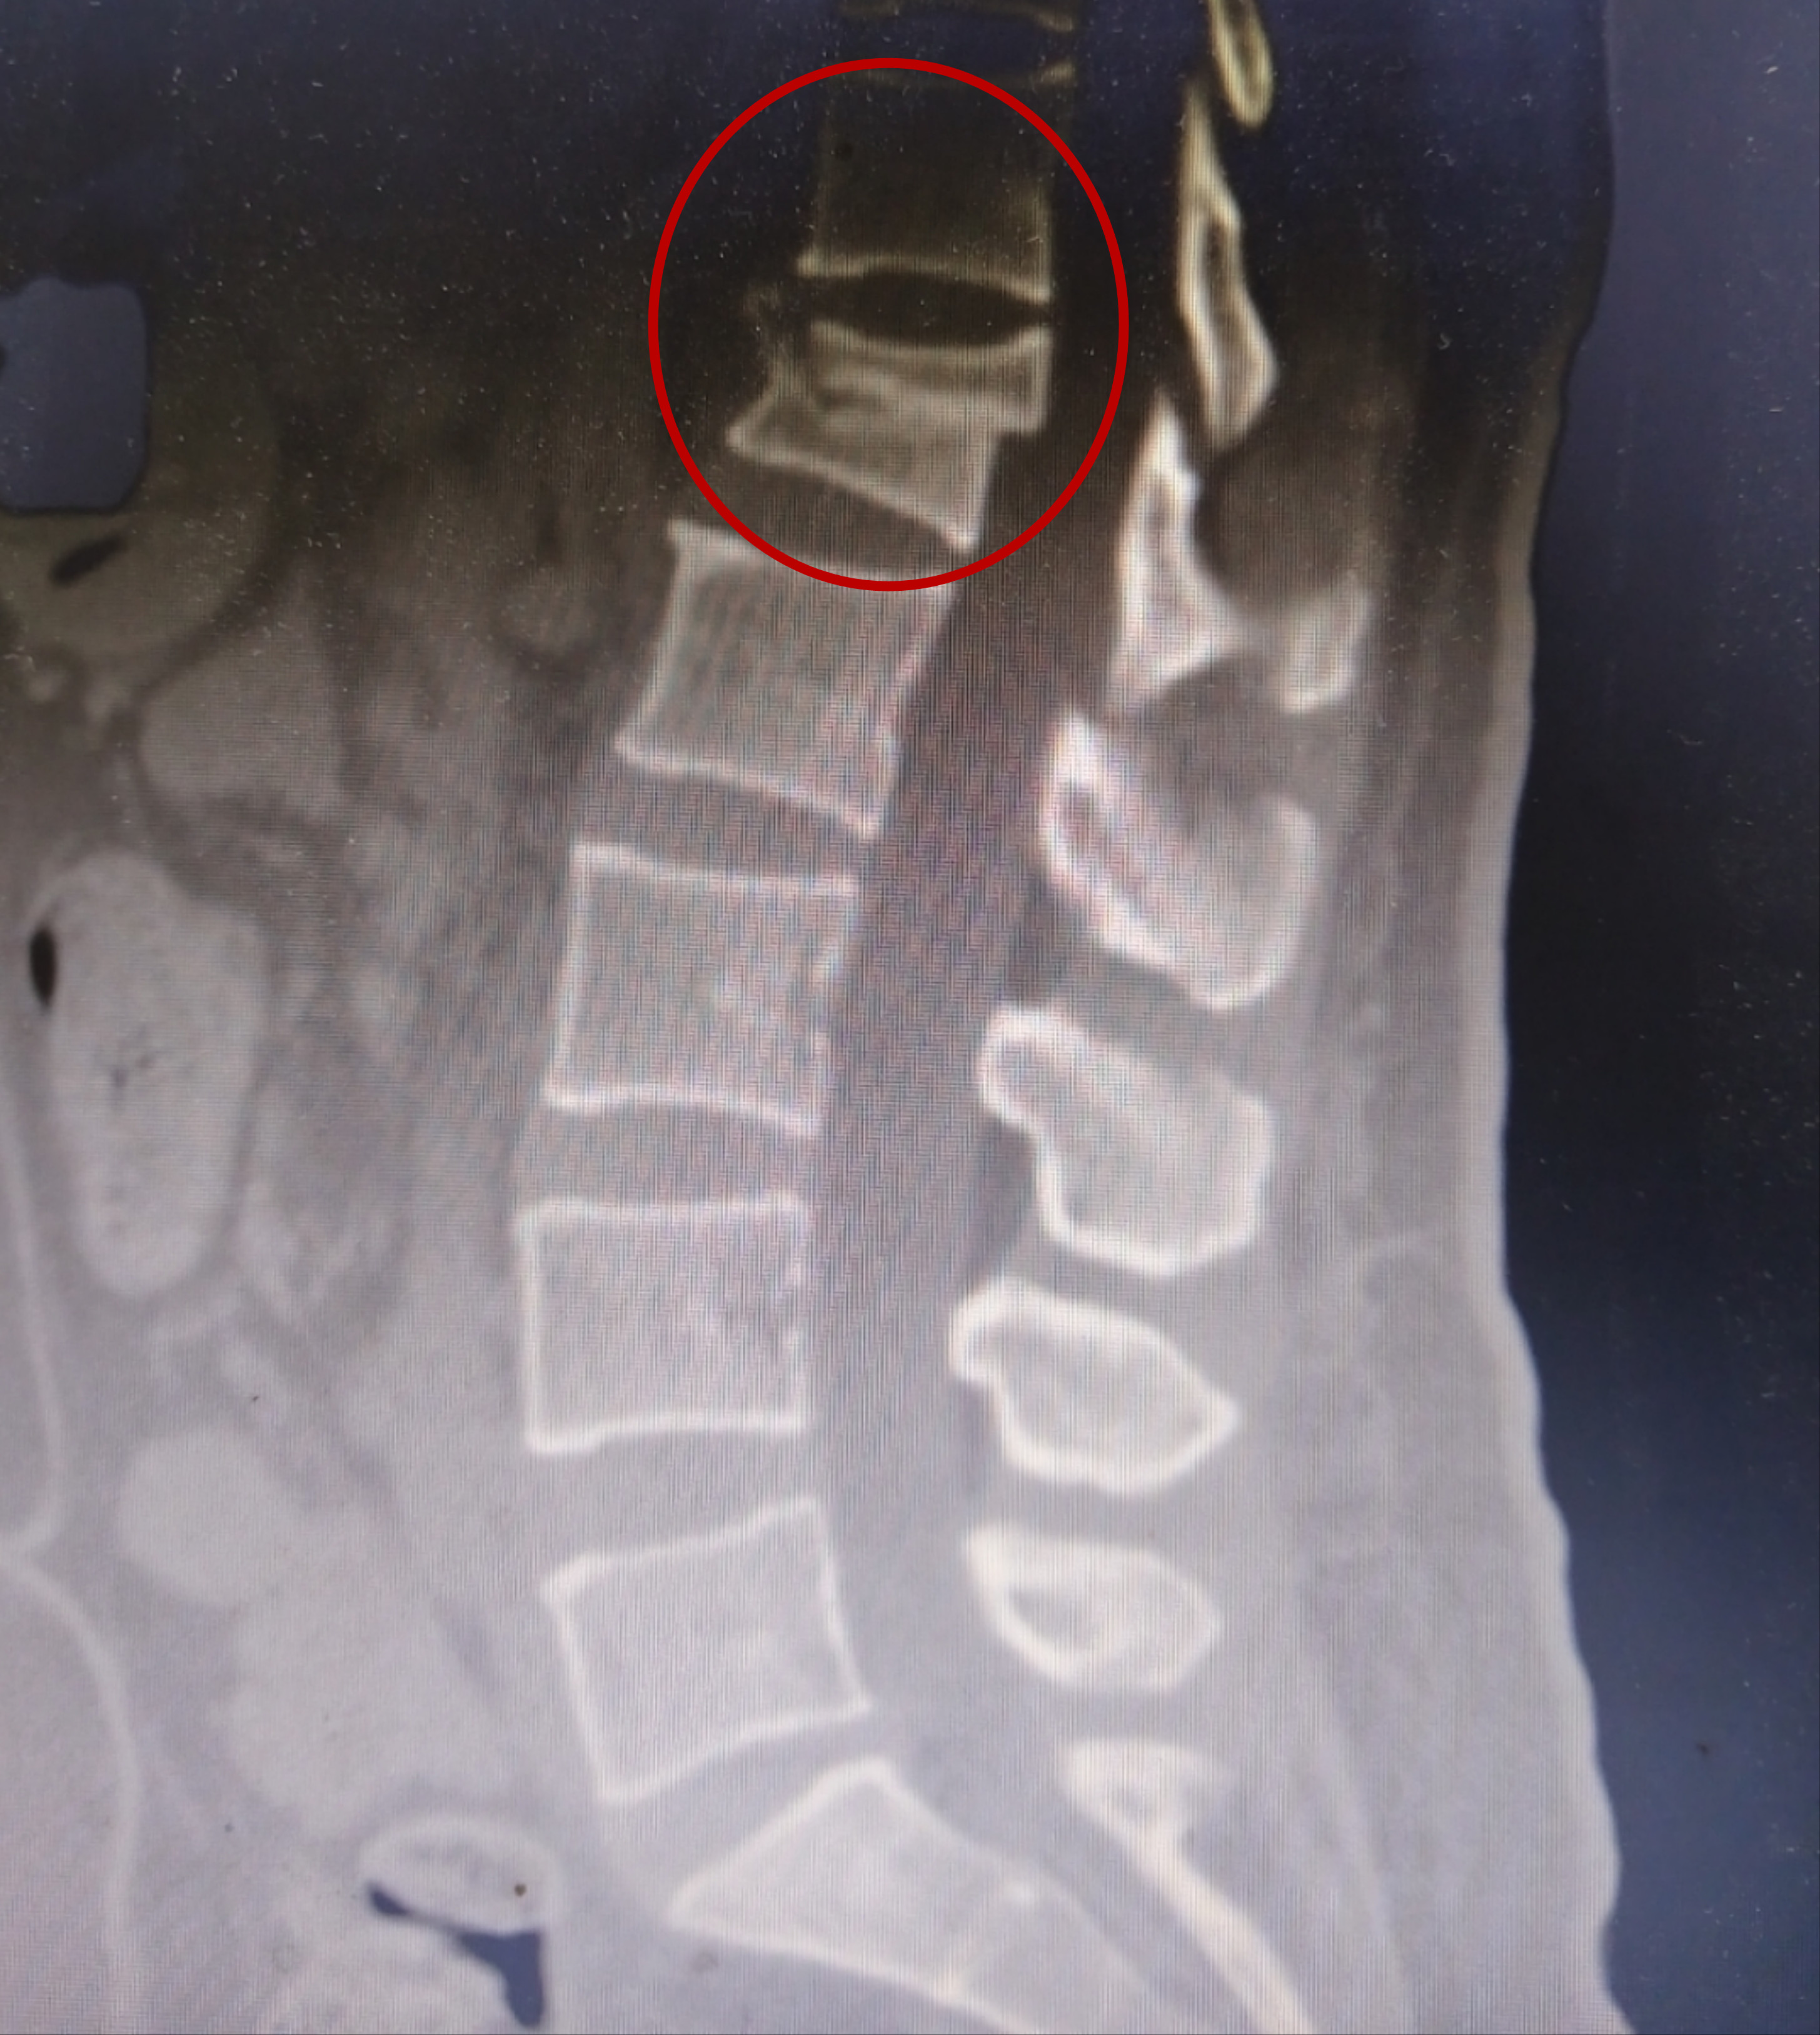

术前检查结果显示王女士腰椎压缩性骨折

前段时间,家住长沙市雨花区的王女士与家人开着越野车开开心心自驾游去西藏。没想到在返回途中,车辆行经一段坑坑洼洼的路面,在路过一个大坑时,车大幅度颠了一下,坐在后排未系安全带的王女士瞬间被腾空抛起,又重重地落回座位上,当即感到腰像断了一样,剧烈疼痛,动弹不得。归家心切的王女士忍着腰痛,强撑到家后才就医,此时距离腰椎受伤已有三天了。果不其然,到捷克论坛 一检查,是腰椎压缩性骨折。为进一步治疗,王女士来到了捷克论坛 骨科五病区住院。

骨科五病区贺学军主任介绍,腰椎压缩性骨折,是腰椎椎体在经受暴力后,产生的一种椎体高度降低的骨折,年轻患者发生腰椎压缩性骨折多因垂直巨大暴力伤引起。像王女士这样,就是在乘车过程中,未系安全带,车速较快,在被抛起后,臀部着地,身体的重量集中在腰椎部位,这才发生了腰椎骨折,同时,王女士长时间暴露在剧烈颠簸的环境中,尤其是持续坐姿不正确,也对腰椎造成压力,增加了骨折的风险。